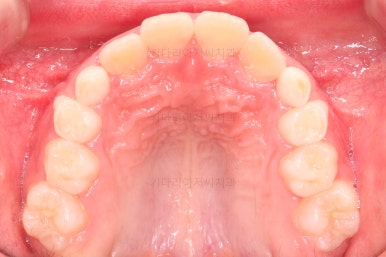

1. 초진

부산어린이교정 키다리아저씨치과에 처음 내원했을 당시의 입안의 모습입니다.

앞니가 거꾸로 물리는 전형적인 앵글씨 3급 부정교합 환아의 모습이었습니다.

아직 유치가 많이 남아 있었꼬, 아래 앞니는 4개가 영구치 맹출, 윗니는 2개가 영구치 맹출 상태였습니다.